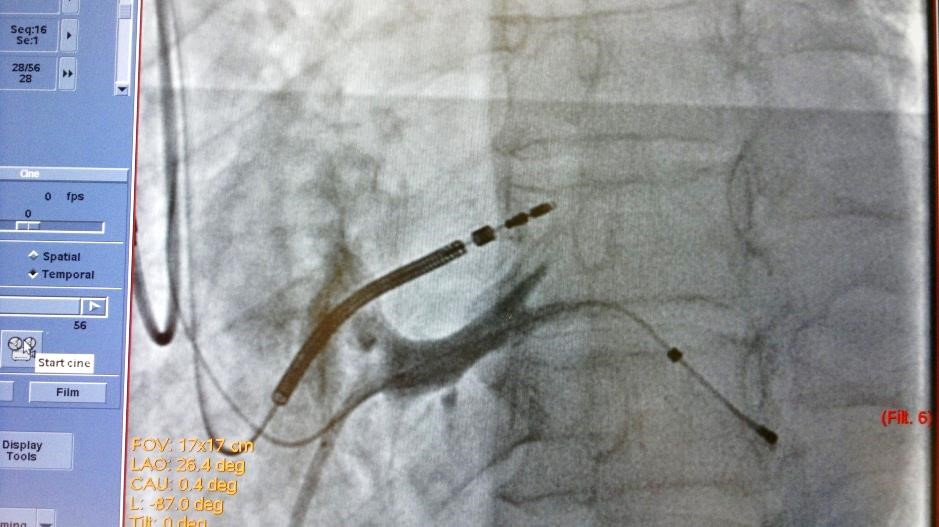

19.08.2015 выполнена попытка имплантации СРТ-D устройства, имплантировать ЛЖ электрод в заднею вену сердца не представилось возможным ввиду многократных смещений ЛЖ электрода в КС. Через 7 дней, вторым этапом, аритмологами и ренгенхирургами принято решение о имплантации ЛЖ электрода в заднюю вену ЛЖ с фиксирующим стентированием ЛЖ электрода в задней вене ЛЖ. Под м/а выполнен разрез в левой подключичной области по п/о рубцу. Выделен и выведен в рану ИКД. Пунктирована подключичная вена из раны. Желудочковый дефибриллирующий электрод активной фиксации позиционирован и вкручен в область МЖП 15 мV (с целью достаточного межэлектродного расстояния) [3], порог стимуляции желудочков 0,8 мА. В ПП по системе доставки доставлен катетер для КС, установлен в КС. Выполнена ангиография коронарного синуса (рис.1) – доступна единственная задняя вена ЛЖ, размером более 4 мм. ЛЖ электрод заведен через систему доставки и установлен в заднюю вену ЛЖ по коронарному проводнику. Порог стимуляции ЛЖ-2.0 мА, порог чувствительности 16.6 мВ. Стимуляции диафрагмального нерва нет. При попытке удаления системы доставки, последний дислоцируется в КС. Множественные попытки имплантации ЛЖ электрода безуспешны в связи с дислокацией последнего. При имплантации в дистальное русло порог ЭКС >6мА. ЛЖ электрод установлен в дистальное русло ЗВЛЖ по коронарному проводнику. Принято решение о фиксирующем стентирование ЛЖ электрода в ЗВЛЖ. Под м/а пунктирована v.f.s., установлен интродьюсер 6 Fr. К устью КС подведен проводниковый катетер JR4 6FR. В дистальное русло ЗВЛЖ проведен коронарный проводник (рис.2). По проводнику в ЗВЛЖ заведен стент 4.5-16 mm, выполнена имплантация (рис.3). При контрольной ангиографии диссекций не выявлено, стент расправлен полностью. Под контролем Rg-скопии и на раздутом баллоне удалена система доставки ЛЖ электрода, ЛЖ электрод стабилен (рис.4), порог ЭКС-0.8 мА (до стентирования 1,5 мА), сенсинг 10 мВ. Электроды фиксированы в ране. Подключен CRT-D и помещен в прежнее ложе над грудными мышцами. На ЭКГ эффективная бивентрикулярная стимуляция.

Рис.4. Финальный рентгеновский стоп-кадр после удаления баллона, проводника и системы доставки ЛЖ-электрода. После фиксации электрода стентом отмечается снижения порога ЭКС на LV электроде до 0,8 мА.